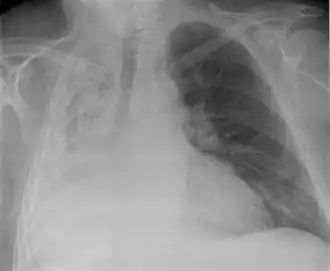

![]() Atelectasia completa del pulmón derecho | ||

- Radiografía del tórax: Detecta los siguientes signos radiológicos:

Signos Directos:

- Retracción de las cisuras lobares.

- Radiopacidad homogénea del lado de la lesión.

- Acercamiento broncovascular.

Signos Indirectos:

- Retracción del Mediastino hacia el lado de la lesión.

- Elevación del hemidiafragma.

- Disminución de los espacios intercostales.

- Enfisema compensador( Hiperinsunflación).

- Desplazamiento del hilio hacia el lado de la lesión.

- Aproximación de las costillas.

En el adulto previamente sano que presente una atelectasia hay que sospechar una neoplasia que obstruye el bronquio. La presencia de todos los signos directos más la mayoría o todos los indirectos confirman la atelectasia.